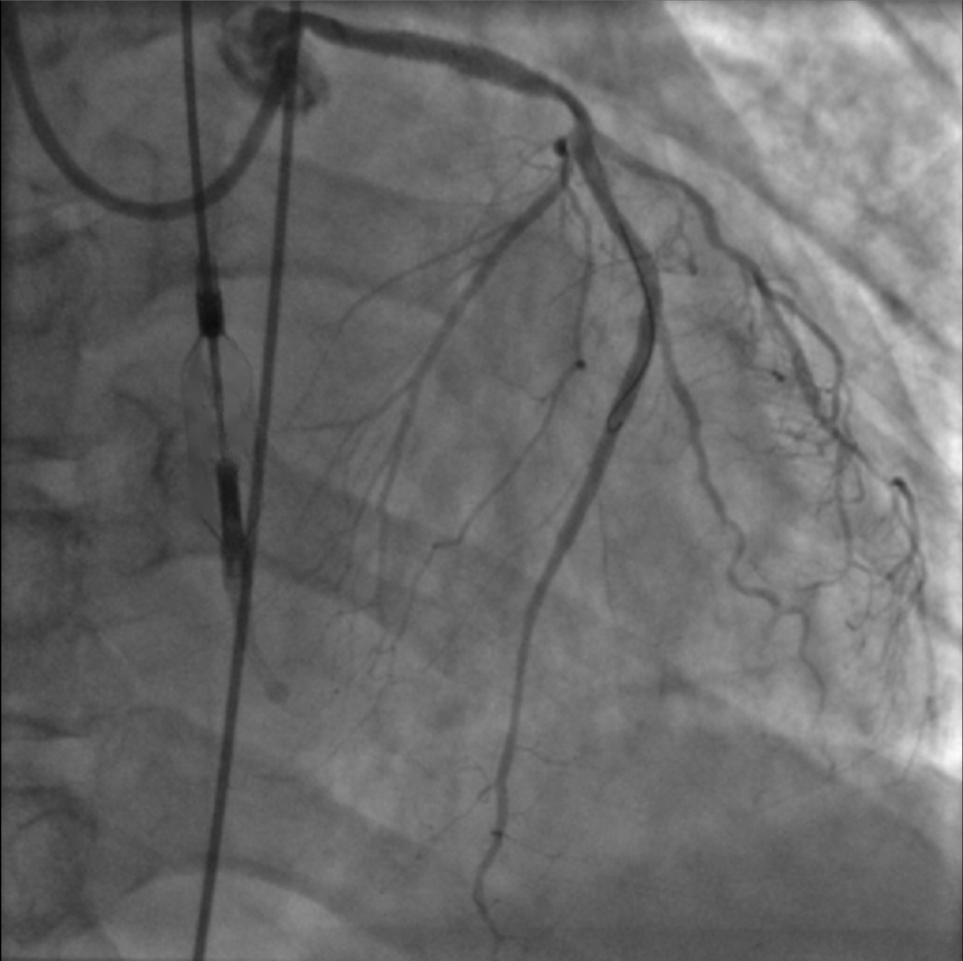

復查造影提示支架擴張滿意,第一對角支殘余狹窄<30%,前降支中段至遠段無殘余狹窄,TIMI血流3級。手術(shù)過程流暢,NyokAssist?操作便捷,過弓、跨瓣性能優(yōu)異,術(shù)中患者血壓平穩(wěn),心超顯示介入泵位置良好穩(wěn)定,主動脈瓣及二尖瓣未見反流加重。

術(shù)后介入泵順利回撤至鞘內(nèi)撤出,僅使用單把ProGlide縫合器完成股動脈穿刺處止血,患者6小時后即下床活動,無血管并發(fā)癥。術(shù)后患者恢復良好,血常規(guī)、肝腎功能等指標均未見明顯異常,術(shù)后動脈血壓維持在130/80 mmHg,術(shù)后心超顯示左室射血分數(shù)改善至36%,未見主動脈瓣及二尖瓣損傷,2天后患者出院。